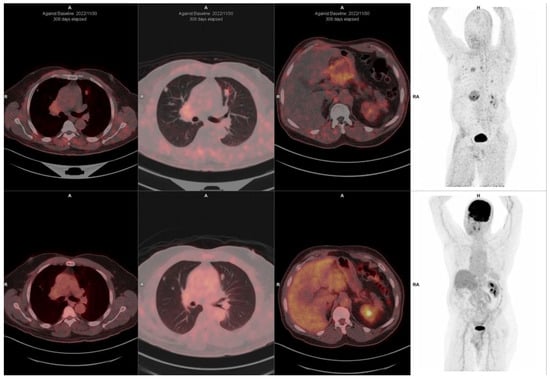

10. FAPI-Based Theranostic Approaches

| Baum et al. [123] | 2022 | Germany | 177Lu-FAP-2286; 68Ga-FAPI-2286; 68Ga-FAPI-04 | 11 patients | 5 pancreas; 4 breast; 1 rectum; 1 ovary. |

| Ferdinandus et al. [124] | 2022 | Germany | 90Y-FAPI-46; 68Ga-FAPI-46 | 9 patients | 3 pancreatic ductal adenocarcinoma; 4 sarcomas, 1 chordoma, 1 neuroendocrine tumor |

| Lindner et al. [34] | 2020 | Germany | 99mTc-FAP-34; 68Ga-FAPI-46; 90Y-FAPI-46 | 2 patients | 1 pancreas; 1 ovarian |

| Lindner et al. [41] | 2018 | Germany | 90Y-FAPI-04; 68Ga-FAPI-04 | 2 patients | 2 breast |

| Ballal et al. [30] | 2021 | India | 177Lu-DOTA.SA.FAPI; 177Lu-DOTAGA.(SA.FAPI)2 68Ga-DOTA.SA.FAP | 10 patients | 5 thyroid; 4 breast; 1 paraganglioma |

| Ballal et al. [125] | 2022 | India | 68Ga-DOTA.SA.FAPI; 177Lu-DOTAGA.(SA.FAPI)2 | 15 patients | 15 thyroid cancers |

| Assadi et al. [126] | 2021 | Iran | 177Lu-FAPI-46; 68Ga-FAPI-46 | 21 patients | 2 ovarian cancer; 2 sarcomas, 3 colon cancer; 5 breast cancer; 2 pancreatic cancer; 2 prostate cancer; 1 cervical cancer; 1 lung cancer; 1 cholangiocarcinoma; 1 thyroid |

| Kuyumcu et al. [127] | 2021 | Turkey | 177Lu-DOTA-FAPI-04; 68Ga-FAPI-04 | 4 patients | 1 breast; 1 thymic carcinoma, 1 thyroid cancer, 1 ovarian cancer |

11. Challenges and Limitations in FAPI Therapeutic Approaches

12. The Potential Role of FAPI PET-Based Theranostic Approaches